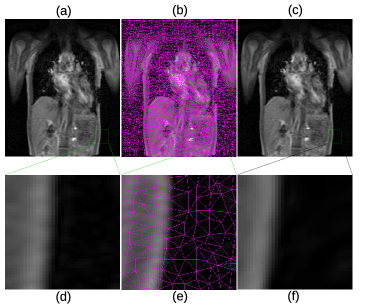

In Fig. 4, more details of the Lena experiment are shown. (a) is the original Lena image, the same as Fig. 3 (a). (b) is the mesh generated by the method outlined in section 2.1. (c) is the recovered image, which is the same as Fig. 3 (e). To visually see the generated mesh and compare the difference between the original and restored images, Fig. 4 (d)–(f) are the zoomed-in views of (a)–(c), respectively. As the results show, the mesh quality is high enough for subsequent numerical analysis and the the recovered image is very close to the original one. As a matter of fact, the restored image looks smoother due to the smooth radial basis functions used, and the sharp edge features are well preserved. Fig. 5 shows the original brain MRI, its generated mesh, and the result of ARBF interpolation using intensities on triangle centers with the MQ basis function. The zoomed-in views show the quality of mesh and restoration as well. Fig. 6 shows another MRI experiment of breast. Fig. 7 shows a CT-scanning experiment. From all these examples, one can see the effectiveness of the proposed approaches for image mesh generation and feature-preserving restoration.